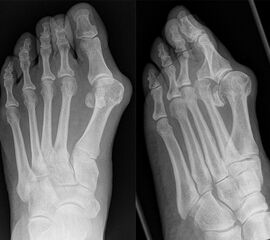

An erster Stelle der bildgebenden Diagnostik steht die konventionelle Röntgendiagnostik. Der betroffene Fuß wird dabei unter Belastung in 3 Ebenen dargestellt. Beurteilt werden der Intermetatarsale-I-Winkel (IM-Winkel), der Hallux valgus Winkel (HV-Winkel), die Lage der Sesambeine, der Arthrosegrad im MTP I Gelenk und ein mögliches plantares Klaffen „gapping“ im Tarsometatarsale-I Gelenk als Hinweis auf eine Gelenkinstabilität. Neben der reinen Beurteilung des Hallux valgus sollten immer auch die Kleinzehen beurteilt werden.

Zum Lesen der Bildbeschreibung und zur Vollansicht bitte das Bild anklicken. Bild: Markus Walther.